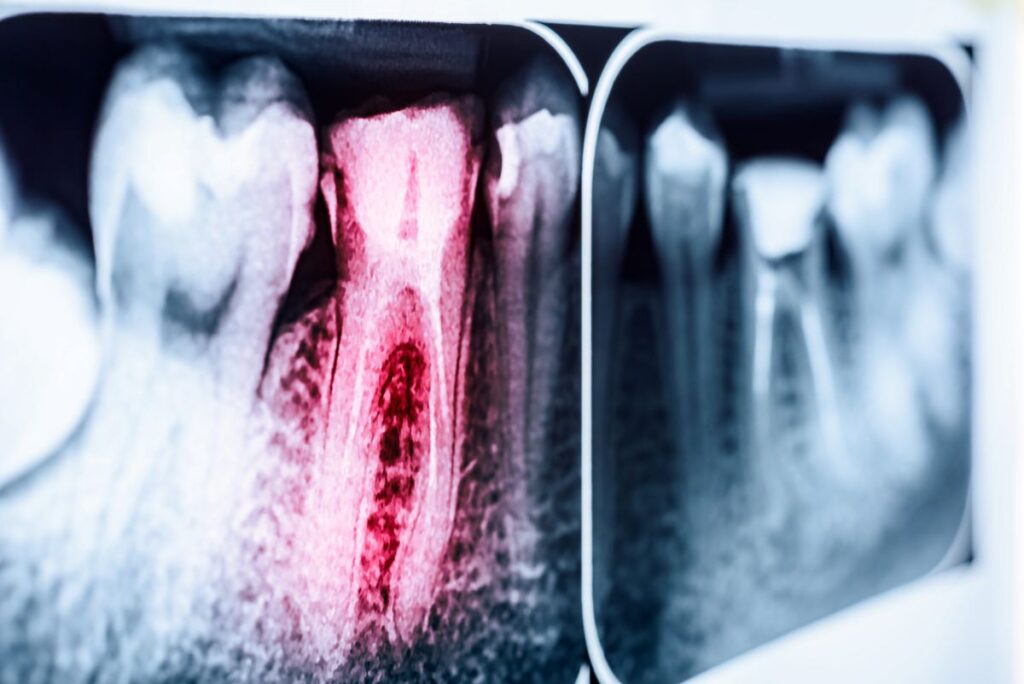

When you know, you know, as they say, and when it comes to needing a root canal due to a painful tooth infection that’s often true. But what happens when your dentist tells you that you need this treatment, despite your smile looking and feeling completely fine? Here’s why a pain free tooth may still require a root canal, even if everything seems normal in your mouth.